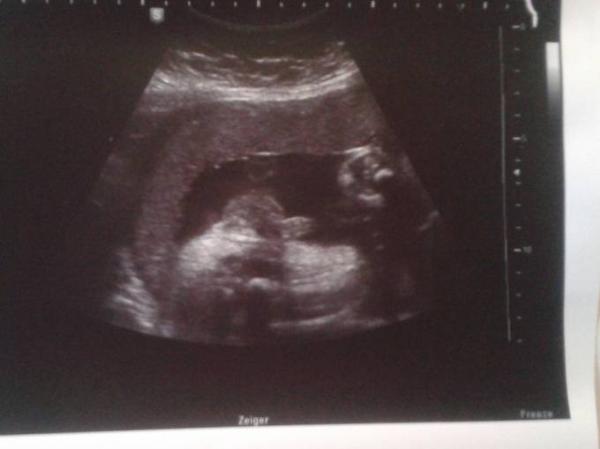

Hallo, ich hatte heute ein Termin bei meiner FÄ und sie hat mir ein Bild ausgedrucht aber leider kann ich überhaupt nicht erkennen was das sein soll bzw. kann ich nicht mal erahnen was für ein Körperteil das ist. Was sieht ihr?

Bild zu Wer erkennt was? - Schwanger - wer noch? Rund um die Schwangerschaft

Welche ssw? So sahen meine pimmelbilder immer aus von meinem Wunder

Hallo Kopf ist rechts dann Bauch und die Beinchen angewinkelt

Sieht nach hoden und penis aus. Der Oberschenkelknochen liegt meiner Meinung unten quer im Bild. Ein Outing hattet ihr sicher schon oder?

Ich habe bereits 4 Jungs und das was ich auf deinem Bild sehe ist eindeutig der kleine Piephahn deines Bubis!